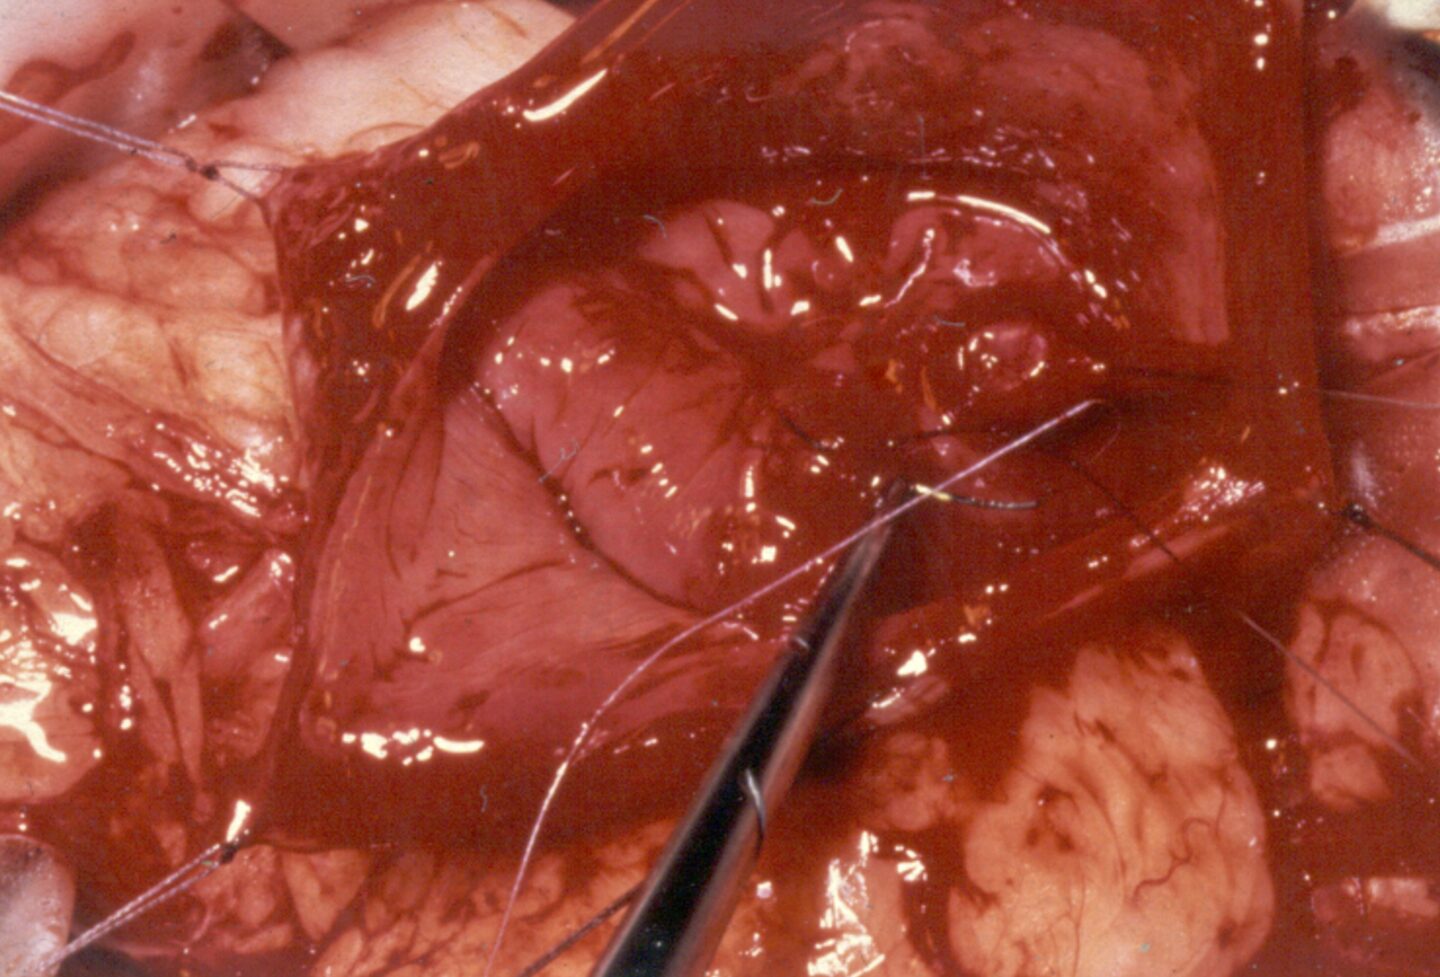

Ektopische Ureteren sind eine selten vorkommende, aber erbliche Erkrankung im Bereich der Mündung der Harnleiter bei Hunden und Katzen. Die Harnleiter münden normalerweise im Trigonium der Harnblase, die Fehlentwicklung führt zu einer weiter kaudal gelegenen Öffnung im Blasenhals, der Harnröhre oder in der Vagina. Bei der häufigen Variante verlaufen die Ureteren intramural, das bedeutet normale Position bis zum Trigoniumbereich, aber dann bildet sich dort keine Mündung, in der Wand (intramural) verläuft der Ureter weiter und mündet weiter kaudal. Beim deutlich selteneren extramuralen Verlauf k